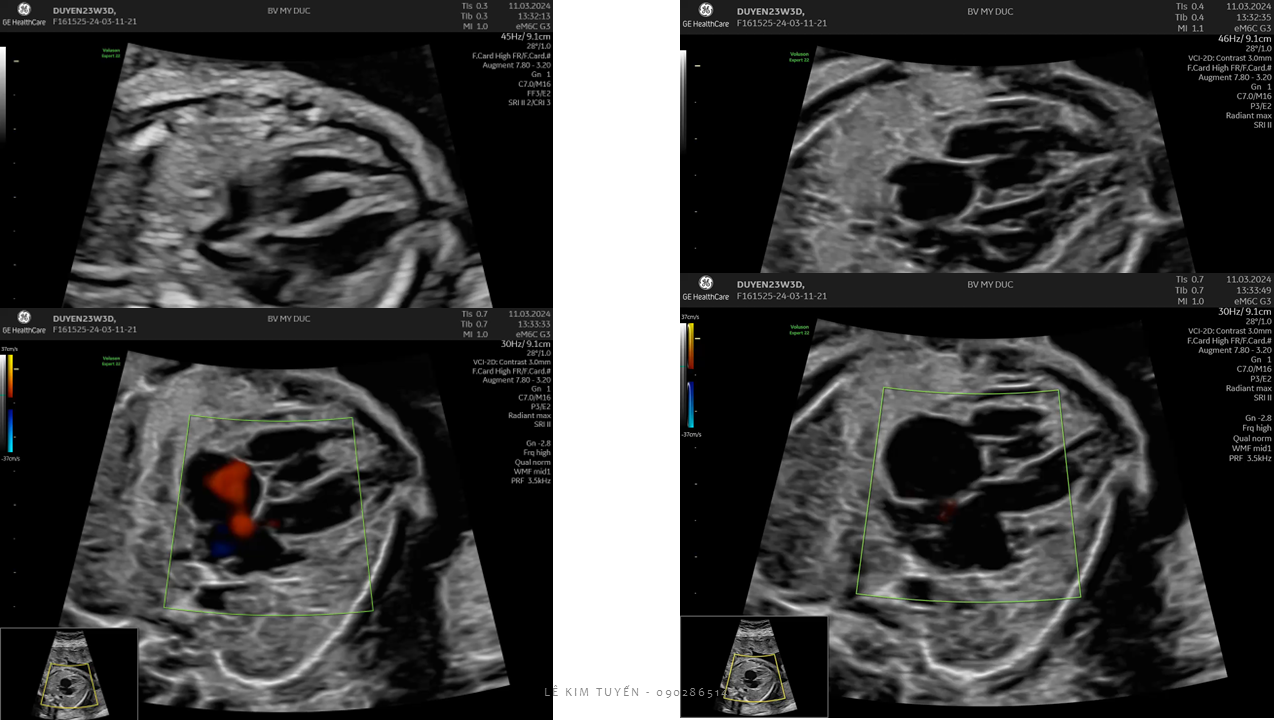

Siêu âm tim thai - Các kỹ thuật hiện đại

TS. BS. Lê Kim Tuyến